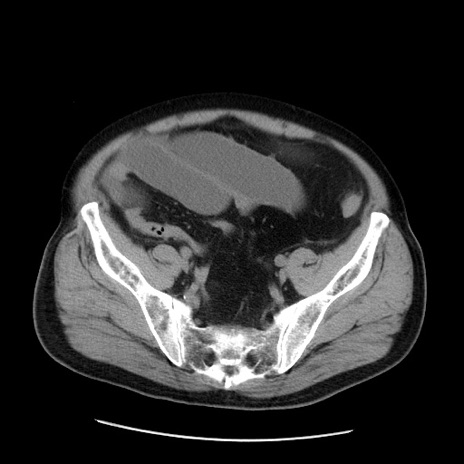

症例20(横断像)

【症例】 60歳代男性

【主訴】 腹部膨満、嘔吐

【現病歴】5日前頃より倦怠感を認め食事量減少し4日前の朝嘔吐、食事摂取困難となった。 3日前近医受診し点滴施行され整腸剤などを処方された。 当日他院を受診し、腹部膨満著明、炎症反応の上昇(CRP10.8、WBC11200)あり、紹介受診となる。

【身体所見】 意識JCS1 受け答えがはっきりしないBP 111/57mHg、 P 67bpm、、BT35.2°C、SpO2 97%(RA)、 腹部:膨隆、打診で鼓音あり、全体的に圧痛有り、腸蠕動音(-)、反跳痛ははっきりせず。

【データ】WBC 11400、CRP 14.20